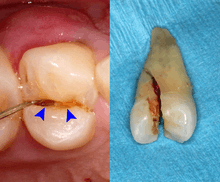

Dental trauma and cracked tooth syndrome

Cracked tooth syndrome refers to a highly variable[29] set of pain-sensitivity symptoms that may accompany a tooth fracture, usually sporadic, sharp pain that occurs during biting or with release of biting pressure,[30] or relieved by releasing pressure on the tooth.[9]:24 The term is falling into disfavor and has given way to the more generalized description of fractures and cracks of the tooth, which allows for the wide variations in signs, symptoms, and prognosis for traumatized teeth. A fracture of a tooth can involve the enamel, dentin, and/or pulp, and can be orientated horizontally or vertically.[9]:24–25 Fractured or cracked teeth can cause pain via several mechanisms, including dentin hypersensitivity, pulpitis (reversible or irreversible), or periodontal pain. Accordingly, there is no single test or combination of symptoms that accurately diagnose a fracture or crack, although when pain can be stimulated by causing separation of the cusps of the tooth, it's highly suggestive of the disorder.[9]:27–31 Vertical fractures can be very difficult to identify because the crack can rarely be probed[9]:27 or seen on radiographs, as the fracture runs in the plane of conventional films (similar to how the split between two adjacent panes of glass is invisible when facing them).[9]:28–9

The prognosis for a cracked tooth varies with the extent of the fracture. Those cracks that are irritating the pulp but do not extend through the pulp chamber can be amenable to stabilizing dental restorations such as a crown or composite resin. Should the fracture extend though the pulp chamber and into the root, the prognosis of the tooth is hopeless.[9]:25